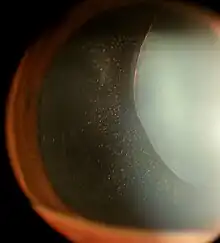

| Ectopia Lentis in Marfan syndrome. Zonular fibers are being seen. | |

Ectopia lentis is a displacement or malposition of the eye's crystalline lens from its normal location. A partial dislocation of a lens is termed lens subluxation or subluxated lens; a complete dislocation of a lens is termed lens luxation or luxated lens.